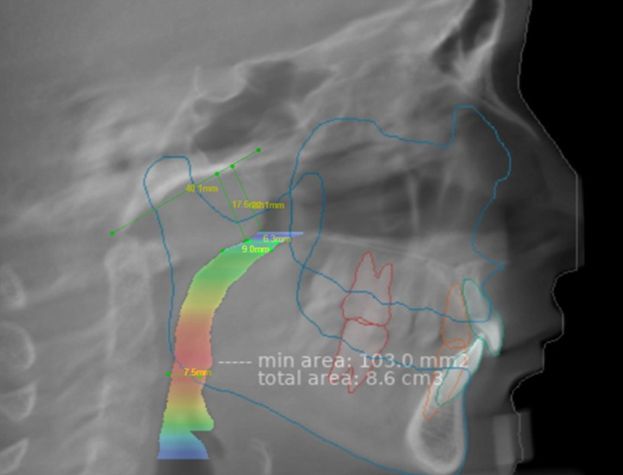

Рисунок 2. Наложение автоматического и ручного расчета верхних дыхательных путей.

Было проведено наложение результатов автоматического и ручного расчёта верхних дыхательных путей (рисунок 2). Надёжность, то есть степень соответствия между двумя методами, составила 93,3 %. Однако было отмечено два особых случая. У двух пациентов из 30 визуализация минимальной площади поперечного сечения (MCSA) и PASmin не совпала.

По результатам статистического анализа коэффициент корреляции Пирсона между PASmin и минимальной площадью поперечного сечения (MCSA) составил 0,289 для группы AG и 0,338 для группы CG. Положительная корреляция между минимальным сагиттальным линейным размером (MSLD) на двумерных реконструированных боковых цефалограммах и MCSA на КЛКТ подтвердила взаимосвязь между этими параметрами.

Однако оценка гипертрофии аденоидов показала низкую эффективность. В отличие от ручной 2D-оценки на реконструированных боковых цефалограммах, Diagnocat не выявлял умеренную или выраженную гипертрофию аденоидов. Искусственный интеллект не определял наличие 2-й или 3-й степени гипертрофии аденоидов по рентгенологическим признакам. Эта важная диагностическая информация может играть ключевую роль при планировании лечения и в достижении ожидаемых результатов. Положительная корреляция между MSLD на двумерных цефалограммах и MCSA на трёхмерных КЛКТ подтверждает клиническую надёжность метода оценки верхних дыхательных путей.